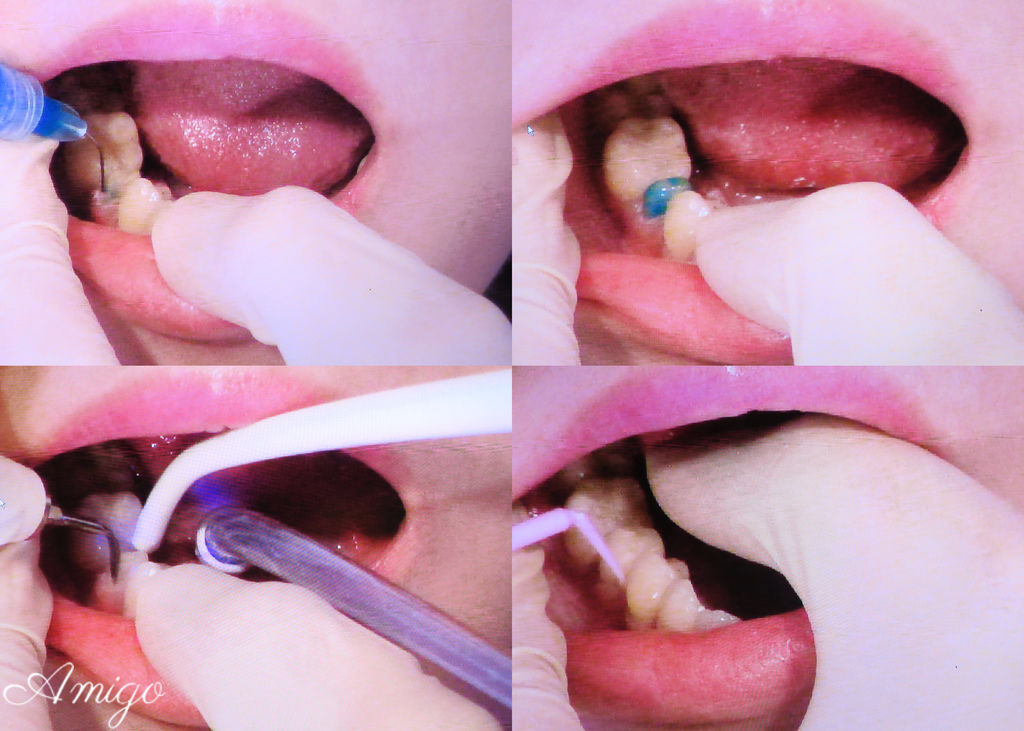

醫師將假牙套放入患者口腔中比對

確認準確度無誤後

再進行標準的消毒清潔的程序

以氫氟酸將全瓷假牙內部進行消毒

口腔內則使用PH值0.5的檸檬酸消毒後沖淨▼▼▼

再次套上牙套後 以專用黏著劑永久黏著

透過取像儀檢視

邊緣的密合度高 加上逼真的全瓷牙冠

幾乎分不出來哪一顆是假牙

最後用光療固定黏著劑

再以色紙確認牙齒的咬合狀況沒有問題

患者便可以開開心心回家~